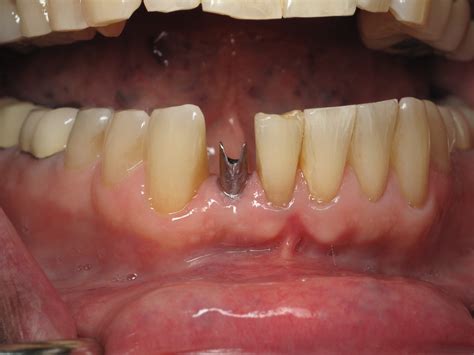

When replacing a front tooth, precision is paramount. The area is highly visible when you smile, speak, or laugh, making the cosmetic outcome just as important as the functional result. Front dental implants are specifically engineered to address the unique challenges of the anterior (front) jaw, where bone density and gum tissue aesthetics are critical.

Implant Placement Surgical insertion of the titanium post into the jawbone.

Osseointegration A healing period of 3–6 months where the bone fuses to the implant.